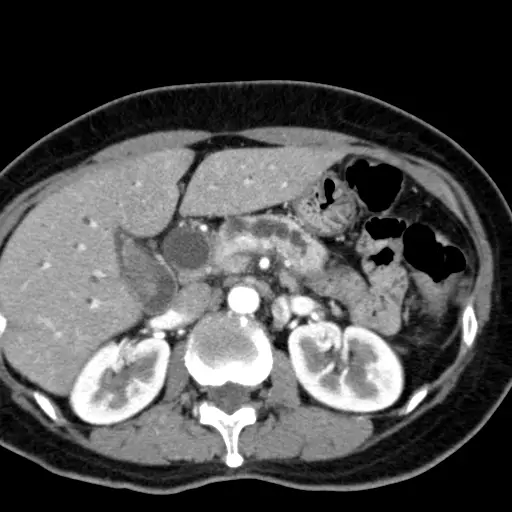

本題考核胰臟頭癌(pancreatic head cancer)的典型臨床表現與影像診斷。老年男性出現疲倦、食慾減退、皮膚黃疸(obstructive jaundice),合併 CA 19-9 升高,搭配 CT 及膽道攝影影像,是胰臟頭癌的典型呈現。

影像一(膽道攝影 / ERCP cholangiogram): 可見肝內膽管明顯擴張,樹枝狀膽道系統顯影清晰,下方膽管出現截斷(abrupt cutoff),符合膽管遠端受壓阻塞的表現。同時可見胰管與總膽管同時擴張的「雙管徵(double duct sign)」,此為胰臟頭部或壺腹周圍腫瘤的高度特徵性影像表現。

影像三(腹部 CT 橫切面,肝臟層面): 肝臟內可見多發性圓形或管狀低密度結構,代表肝內膽管(intrahepatic bile ducts)瀰漫性擴張(int